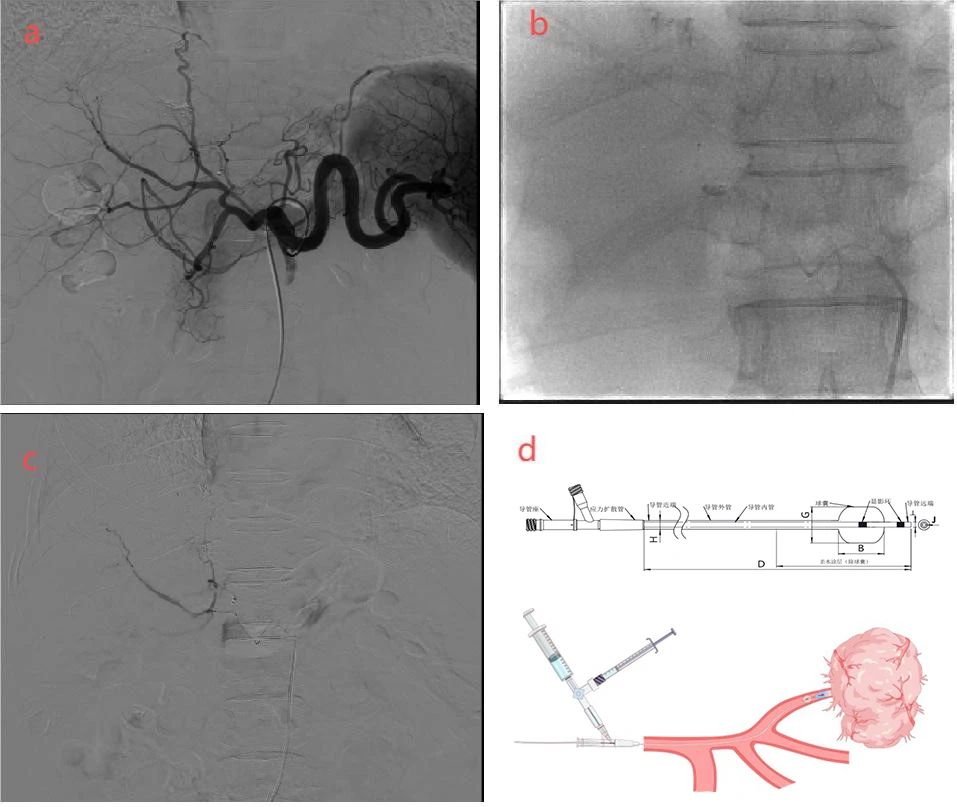

a :肝动脉造影显示肿瘤区域乏血供浅淡染色;

b:球囊导管超选到肿瘤供血动脉近端,球囊充气阻断后加压注入栓塞剂;

c:栓塞后造影肿瘤血管淤滞;

d :Hiflamingo®球囊导管结构及工作示意图。